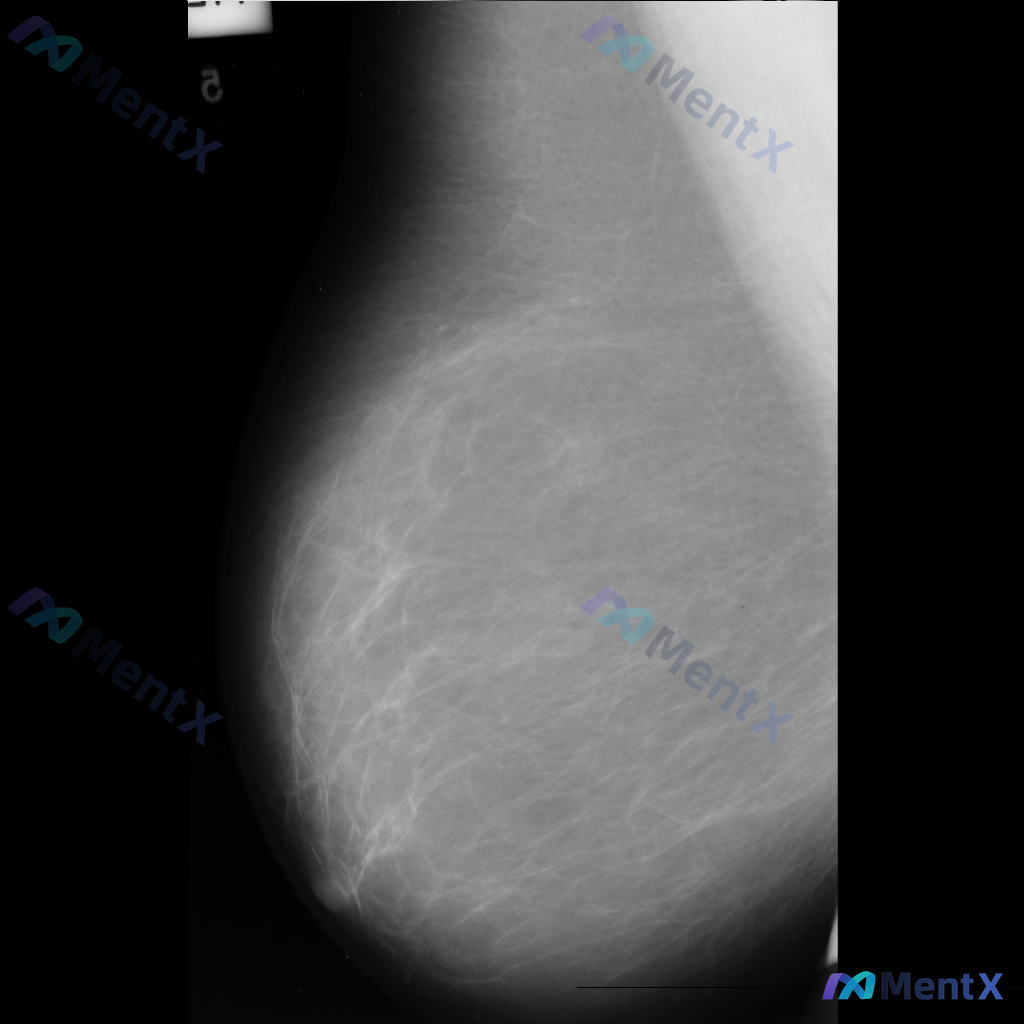

整理到一份单张的乳腺钼靶影像资料,仅有单侧、单幅图像,没有对侧对照,也不确定是MLO位还是CC位。 目前能看到的信息大概是: - 乳腺类型看起来是多量腺体型 - 图像上没有看到明确的肿块、可疑的恶性钙化 - 皮肤、乳头、血管这些能看到的部分没有明显异常(不过图像范围没包含腋窝) 这种情况下,大家觉得...